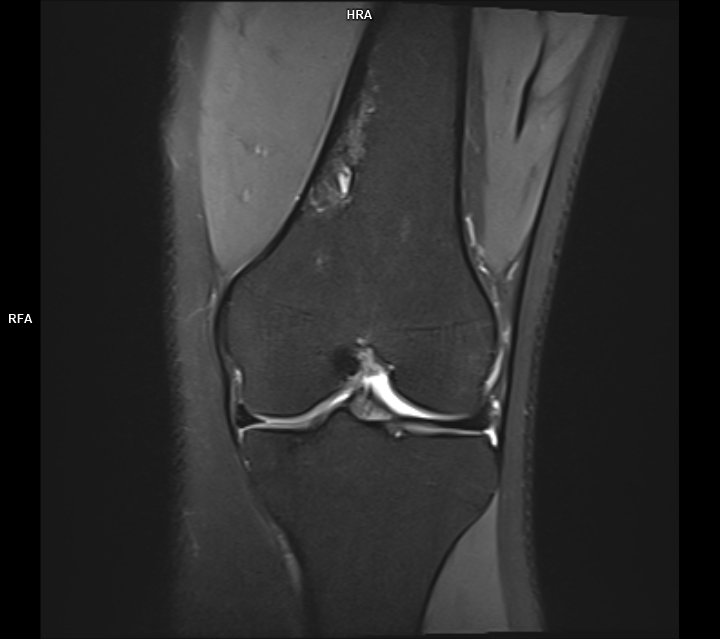

Figura 5, 6: achiziție PD FS coronal